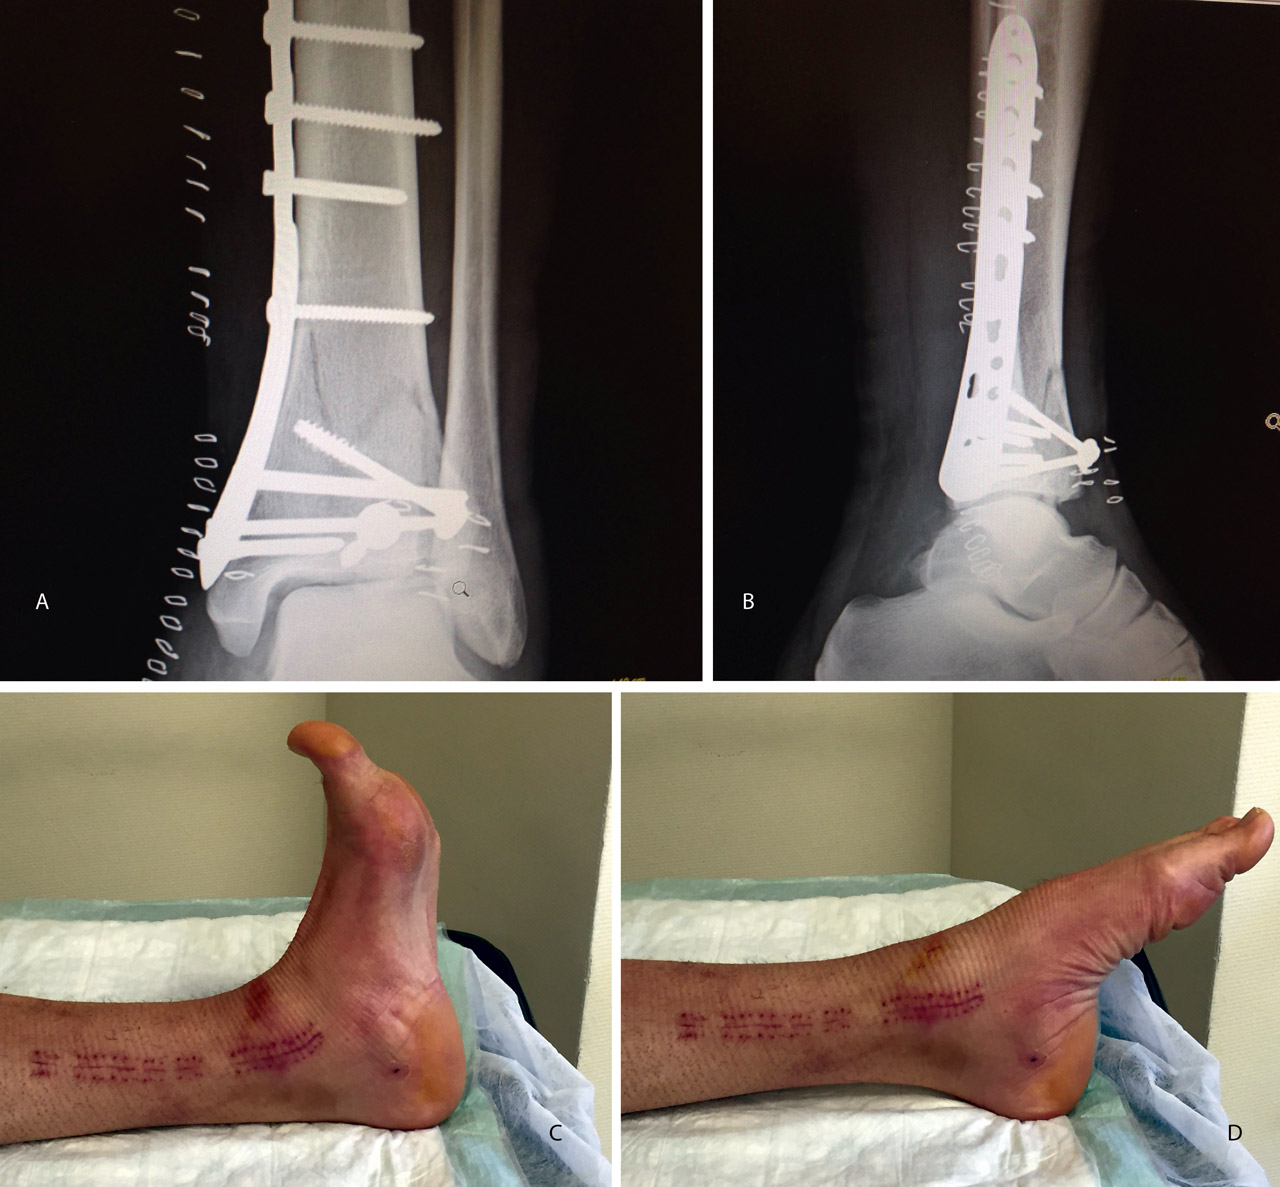

Figura 20. Radiografías postoperatorias y resultado final con movilidad completa en flexoextensión del tobillo.